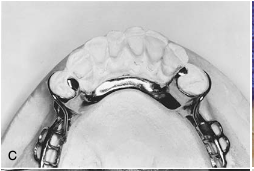

palatal major connector [illustration]

metal lingual bar major connector [illustration]